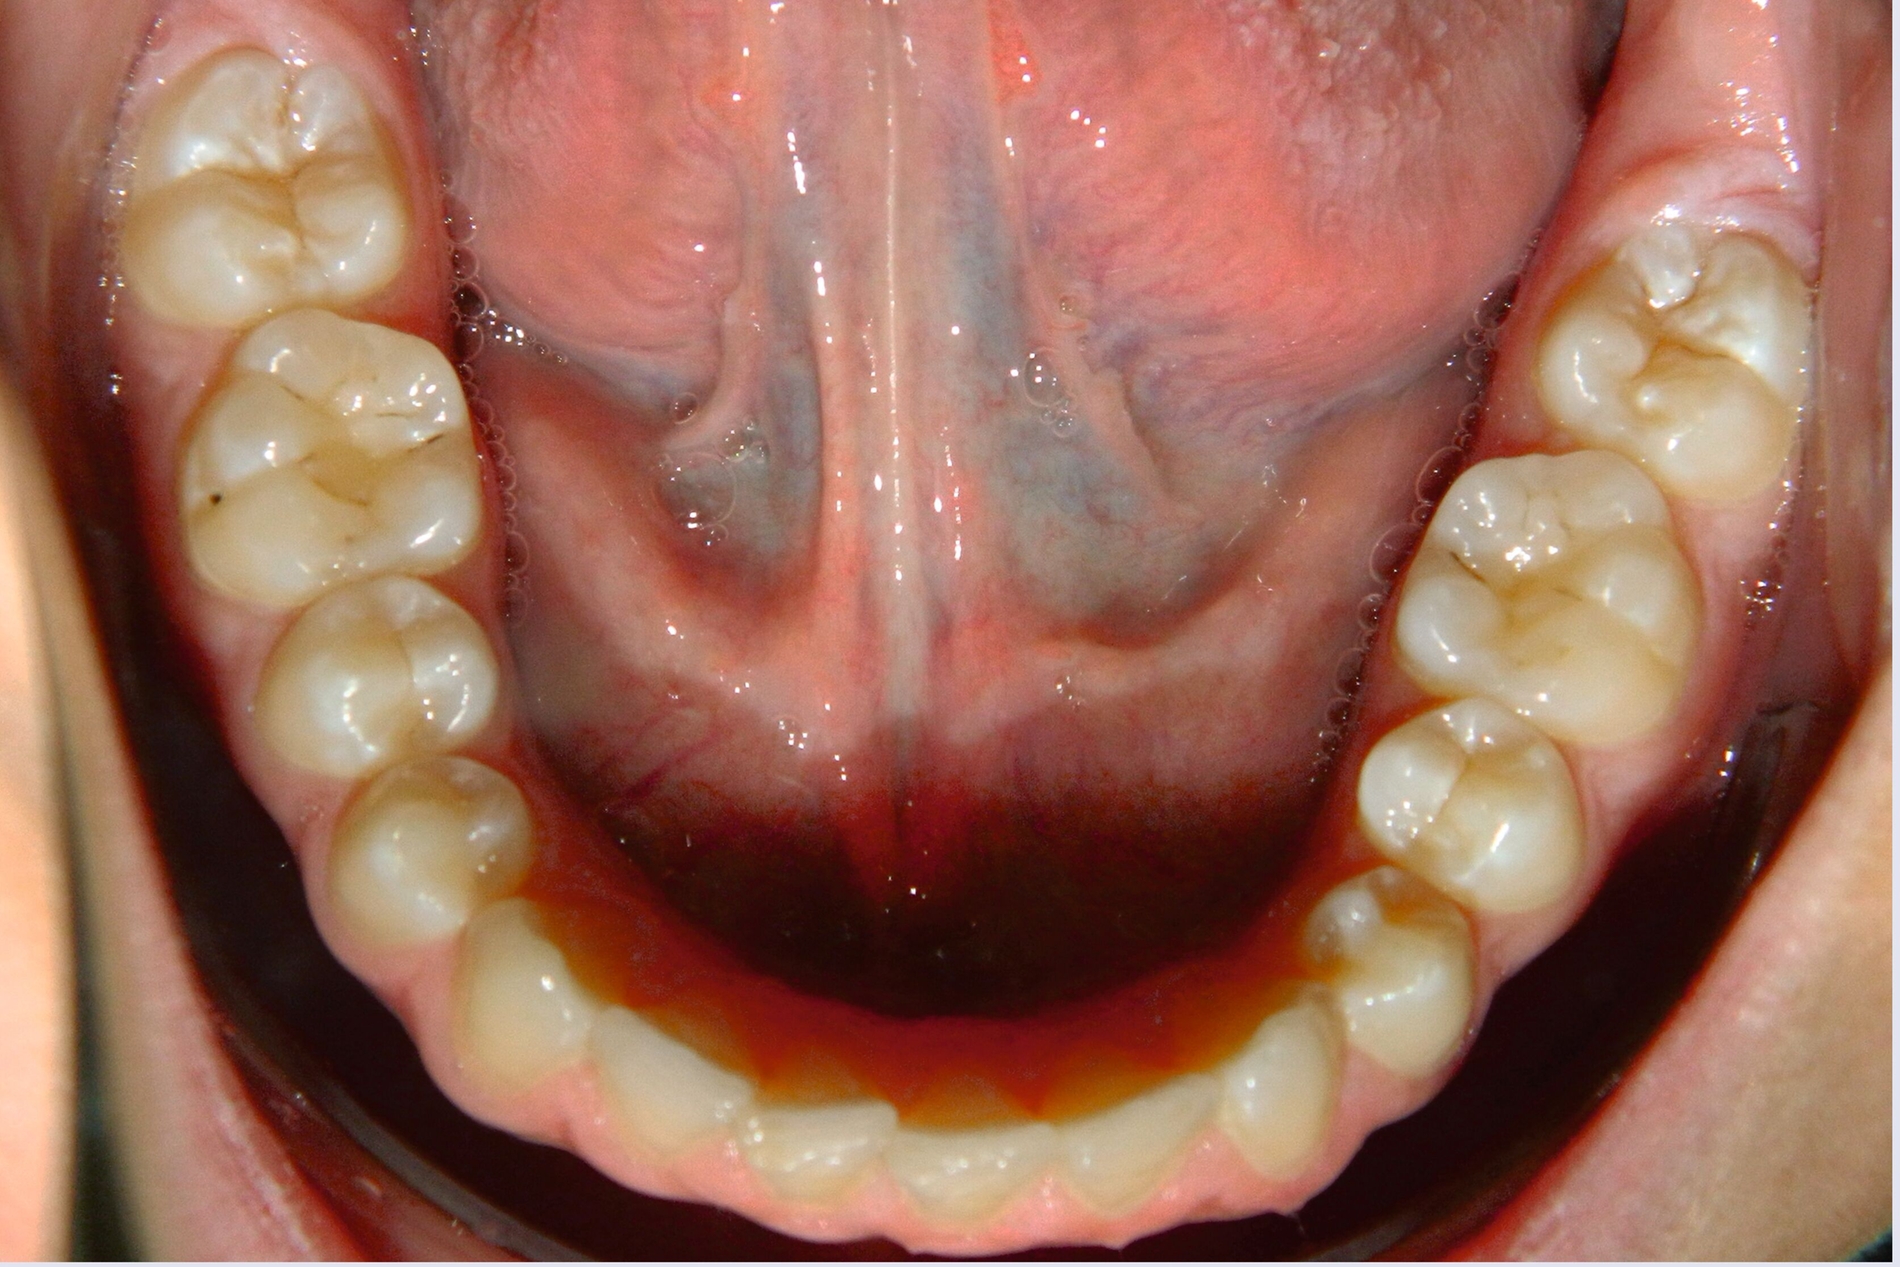

Um die Position des impaktierten Eckzahns zu beurteilen, wurde zehn Monate nach der Extraktion des Schneidezahns eine weitere Panoramaröntgenaufnahme angefertigt, Die Position des Eckzahns war unverändert, jedoch hatte die Extraktion des impaktierten oberen Schneidezahns zu einer signifikanten Knochenresorption und Atrophie des Alveolarkamms (Abbildung 3) geführt.